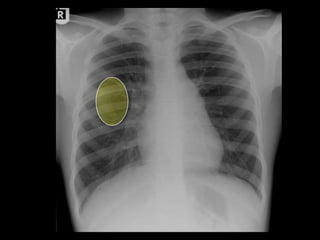

This document provides an overview of normal musculoskeletal imaging. It discusses basic x-ray concepts and densities. It then reviews normal anatomy as seen on x-rays of the skull, spine, pelvis, chest, and extremities. Key anatomical structures are labeled on example x-rays for the shoulder, hip, knee, and foot. Quizzes are included to test recognition of anatomical structures and patient age based on x-rays.